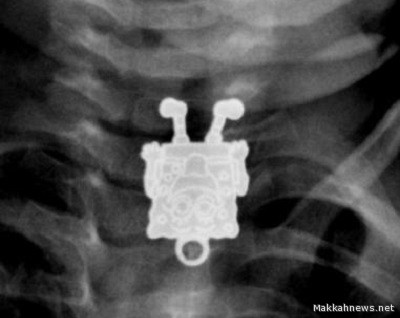

تمكن الأطباء في مستشفى الملك عبدالعزيز بجدة من استخراج لعبة “سبونج بوب” – الشخصية الكرتونية المعروفة – من مريء رضيع يبلغ من العمر 16 شهراً.

وأحضر أب طفلهُ الرضيع إلى المستشفى، مخبراً عن أنه ابتلع قطعة غير معروفة، وبإجراء الأشعة فوجئ الأطباء بوجود لعبة”سبونج بوب” داخل مريء الطفل.

وعلى الفور أجرى الأطباء جراحة للطفل الرضيع، وتم استخراج القطعة قبل أن تسبب تهديداً لحياته.

من جانبها، نشرت إحدى أخصائيات الأشعة بمستشفى الملك عبدالعزيز صوراً للحالة بأحد المواقع المتخصصة في الأشعة، مشيرة إلى أنها للوهلة الأولى بعد اطلاعها على الصورة الجانبية ظنت أن الطفل ابتلع قلماً، إلا أنها تفاجأت بعد ذلك من الصور الأمامية بأنها قلادة على شكل “سبونج بوب”.